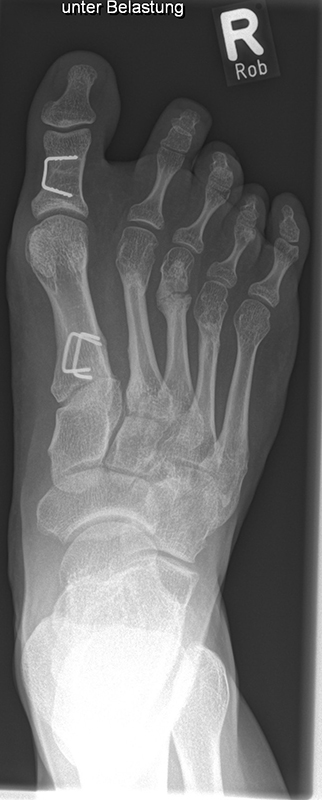

In der Regel bestehen aktive Wachstumsfugen bei Mädchen bis zum 12. und bei Jungen bis zum 14. Lebensjahr, mit Abweichungen von einem Jahr nach unten und nach oben. Präzise Informationen unter anderem darüber gibt das präoperative Röntgenbild (Abb. 2).

Abb. 2 a-c: offene Wachstumsfugen MT I Basis und Zehen (a), teilweise geöffnete Wachstumsfugen (b) und geschlossene Wachstumsfugen (c).